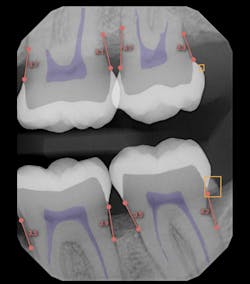

AI radiographic interpretation is gaining traction across dentistry. It helps clinicians detect pathology, guides decisions (remineralize vs. restore), and quantifies decay and bone loss for stronger third-party justification.17 AI also enhances patient education by making radiographs easier to understand visually (figure 3).